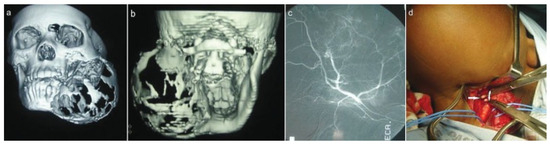

Imaging studies included chest radiographs, an orthopantomograph, posteroanterior mandibular radio-graph, computed tomography (CT), and CT angiogram (Figure 1c,d and Figure 2a–c). The chest radiographs were normal. The orthopantomograph showed an expansile lesion of the left side of the mandible involving the ramus and body with associated displaced and floating teeth. CT studies included 1.5 × 3-mm overlapping axial cuts, 5 × 5-mm coronal cuts through the same region, and 5 × 5-mm spiral axial scans through the mandible after contrast administration. Imaging studies showed a large expansile multilocular cystic mass involving the left mandible. The mass measured 8 × 9 cm and 152 to 158 Hounsfield units, which was diagnostically suggestive of a vascular lesion radiologically. There were septae and some enhancing soft tissue components within the mass. The lesion extended to the nasopharynx and oral cavity medially, to the base of the skull superiorly, and to the parotid and carotid spaces posteriorly. There was no intracranial involvement. The patient was booked for incisional biopsy. Prior aspiration of the lesion was positive for blood, which appeared to be of a high-flow nature. To avoid the possibility of uncontrollable intra-operative bleeding, the procedure was abandoned. Based on the imaging studies, a provisional diagnosis of an ABC was made. Attempted shrinkage of the lesion was considered with the use of embolization. The patient was therefore referred to an interventional radiologist for possible embolization of the lesion. Embolization of the internal maxillary artery on the left side was done with 100- to 300- as well as 300- to 500-size contour particles. A silicone SL14 catheter (Jet Medical South Africa, Gauteng, Cape Town, KZN, South Africa) with a Silver Speed guide wire (Micra Therapentics, Inc., Irvine, CA) was used to do superselective embolization of the feeding vessels to the tumor. An angiogram done at this stage showed a highly vascular mass in the left mandible. The patient was unable to keep to the regular appointments due to financial constraints and therefore presented herself 3 months after embolization. The lesion was found to have increased in size. New CT scans confirmed that the lesion had increased in size and was still highly vascular. A decision was taken to surgically remove the lesion after ligation of the ECA with immediate reconstruction of the mandible. Postresection reconstruction was preplanned using stereolithographic models to achieve maximum preoperative symmetry and function.

Figure 2. (a,b) 3-D computed tomography (CT) reconstruction views. (c) CT angiogram during embolization. (d) Exposed external carotid artery (arrows).